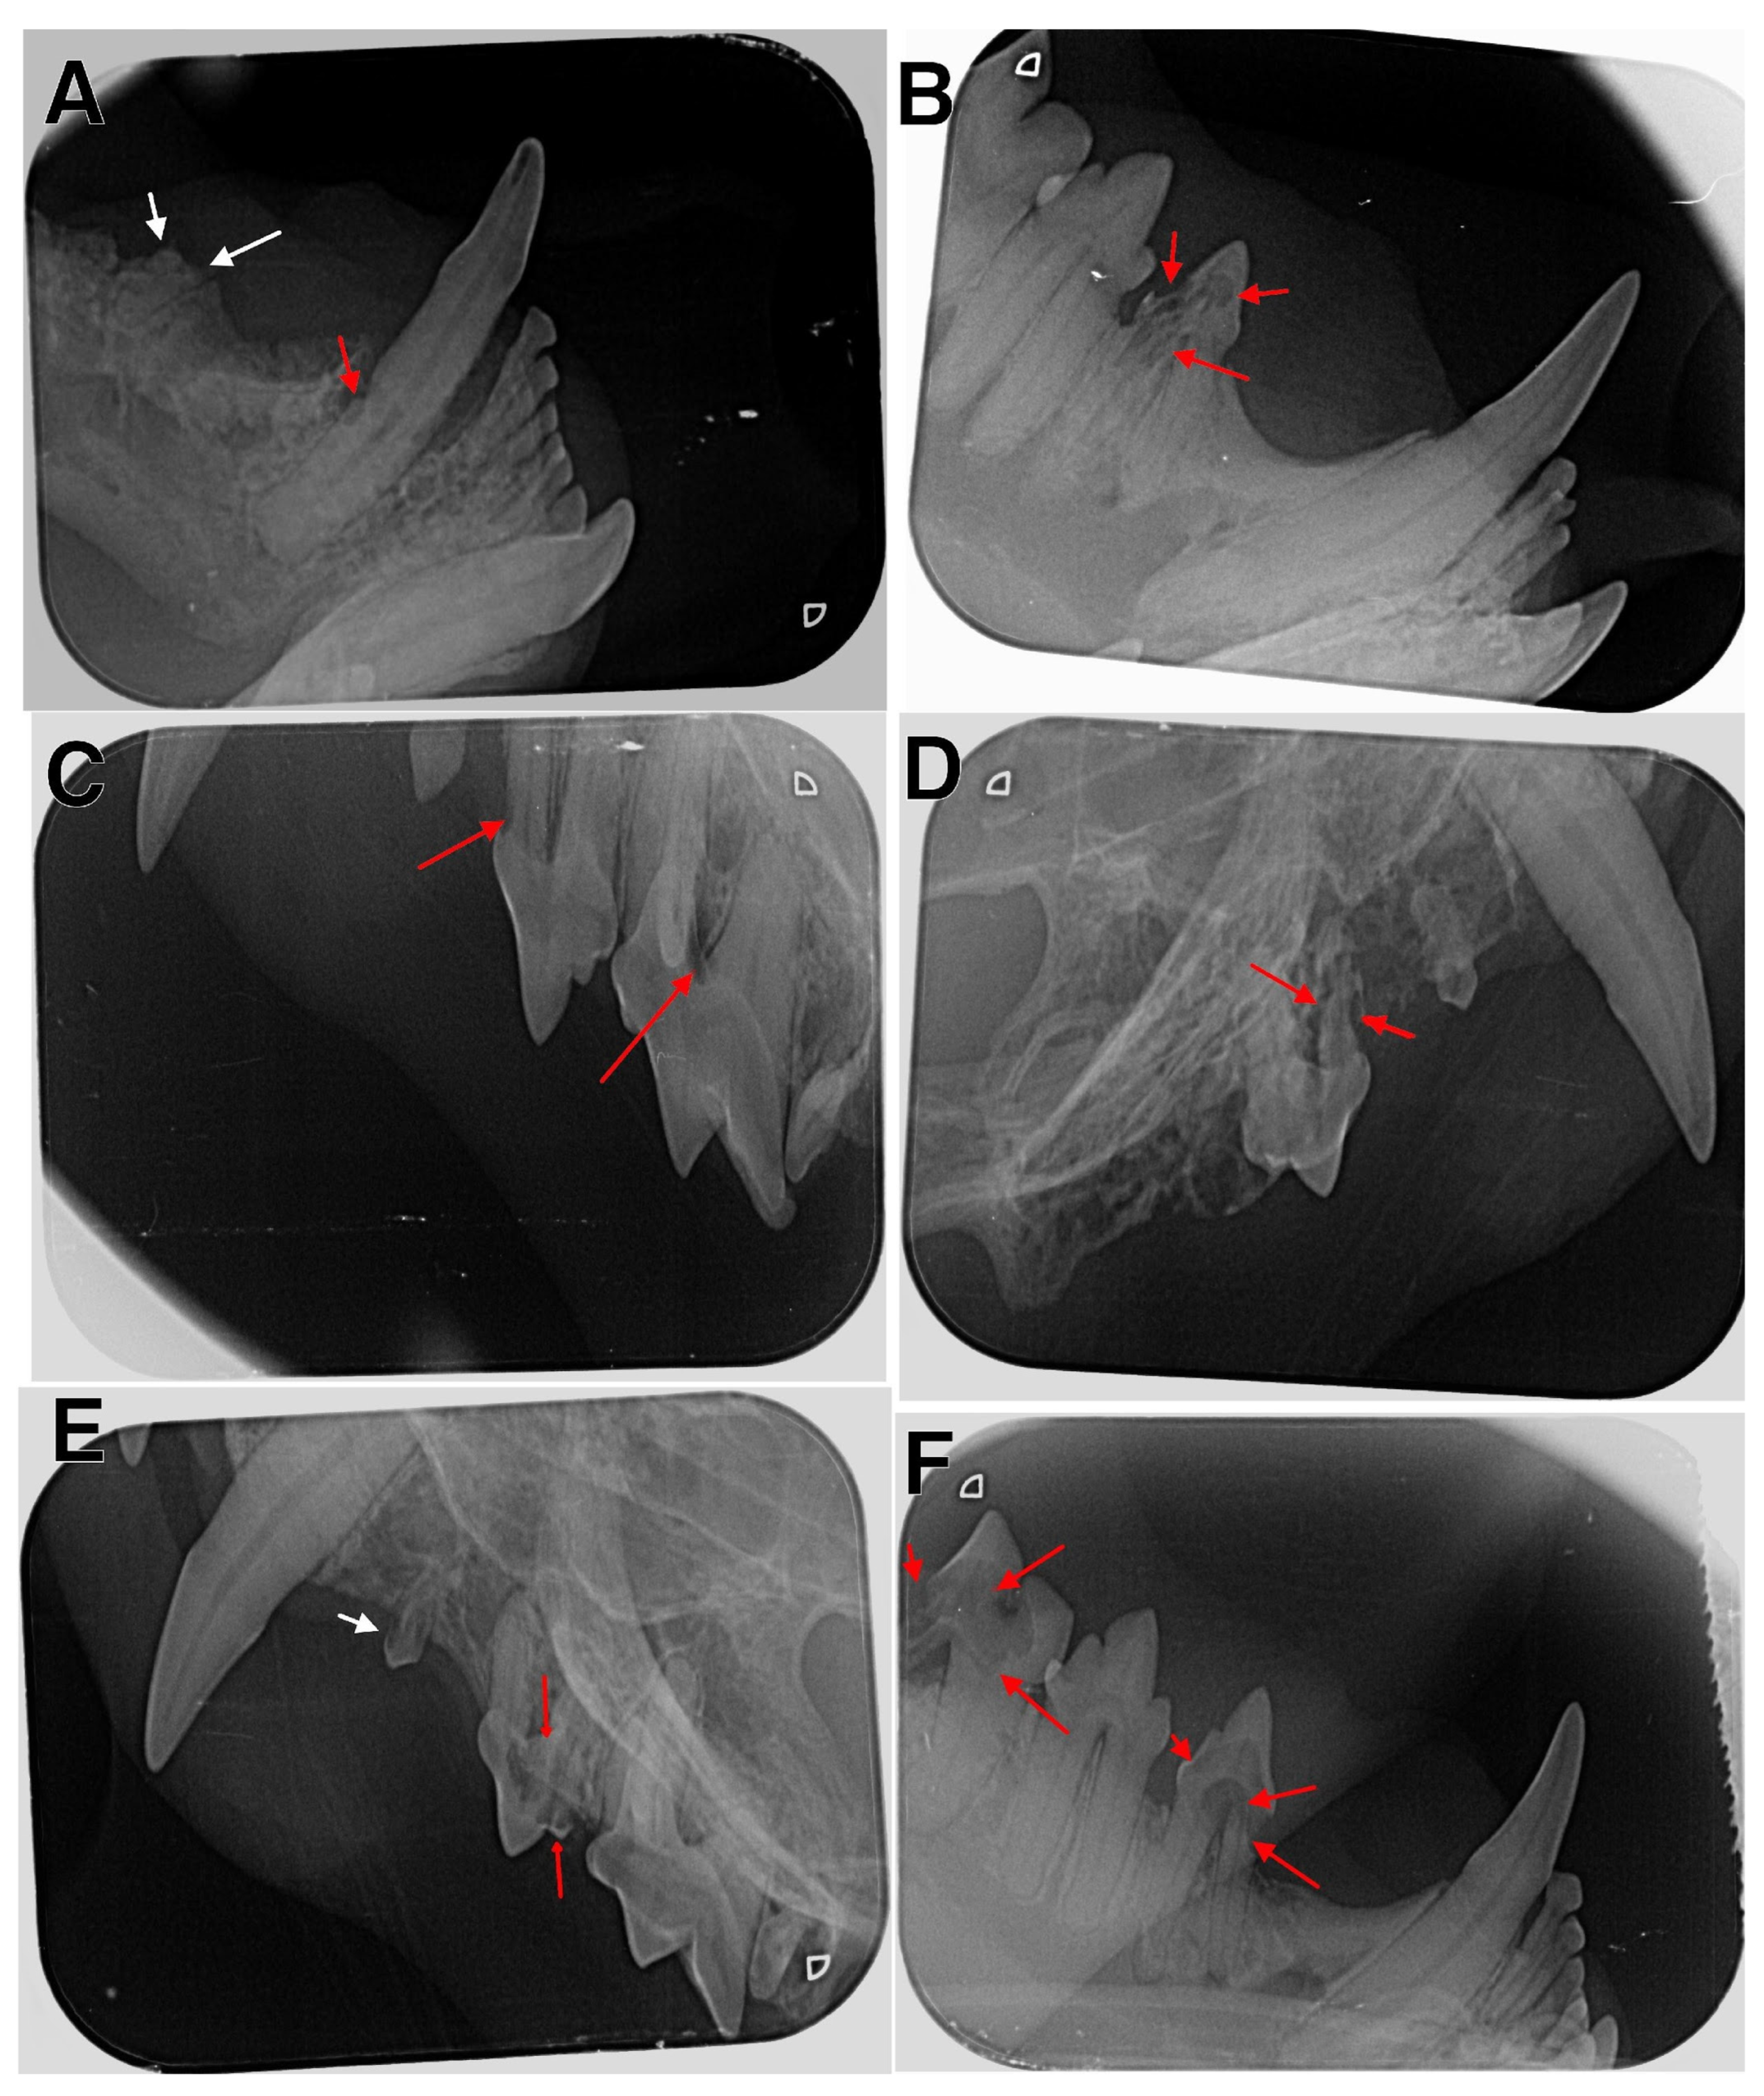

Figure 3.

Radiographic examination of affected cats. (A) The right mandible with type 2 lesion in tooth 404 (red arrow) and type 5a lesion in tooth 407 (white arrows); (B) the right mandible with type 4 lesion in tooth 407; (C) the left maxilla with type 1 lesions in teeth 207 and 208 (red arrows); (D) the right maxilla with type 4 lesions in tooth107 (red arrows); (E) the left maxilla with type 1 lesion in tooth 206 (white arrow) and type 4 lesions in tooth 207 (red arrows); (F) the right mandible with type 4 lesions in teeth 407 and 409 (red arrows).